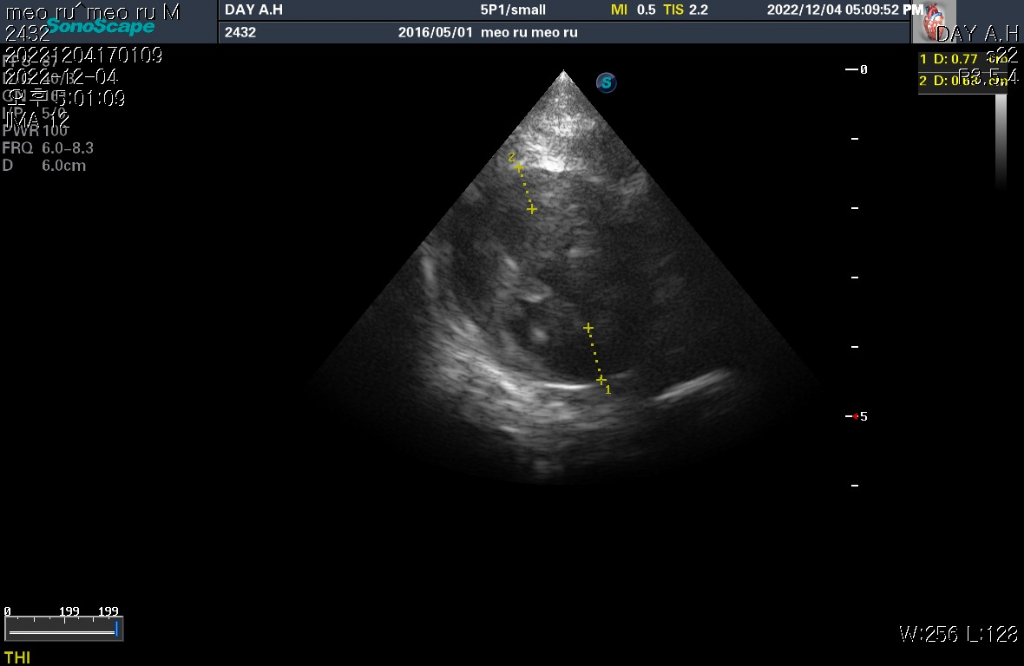

하지만 심장 질환의 잠정적 확진 golden standard는 심장 초음파 검사로 심장 초음파 검사상 심장의 벽 구조가 6mm이상이라면 HCM의 가능성이 매우 높다고 판단합니다.

현재 첨부한 사진상에서 6mm이상의 직경을 보이는 사진들이 존재하기 때문에 해당 검사를 진행한 수의사의 기준상 HCM의 가능성이 높다고 판단하는것은 합리적입니다.